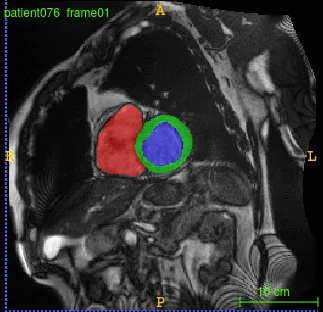

We developed a deep learning based framework for cardiac segmentation which incorporated cardiac structures segmentation and cardiac disease diagnosis. The figure below illustrates the pipeline. The pipeline involved:

- FCN for cardiac structures segmentation: A typical semantic segmentation architecture comprises a down-sampling path (contracting) and an up-sampling path (expanding).

By following these steps in framework and network design, we achieved almost state-of-the-art performance on multiple cardiac segmentation datasets namely- (i) On STACOM ACDC-2017 challenge test set for segmentation task achieved a mean dice score of 0.94, 0.91 and 0.89 for the left ventricle, right ventricle and myocardium respectively and for automated cardiac disease diagnosis the accuracy was 100%, (ii) On STACOM LV-2011 test set the approach achieved 0.74 Jaccard index for myocardium segmentation. On the Kaggle challenge test set, the approach gave a continuous ranked probability score (CRPS) of 0.0127 for left ventricular volume estimation.

Prediction